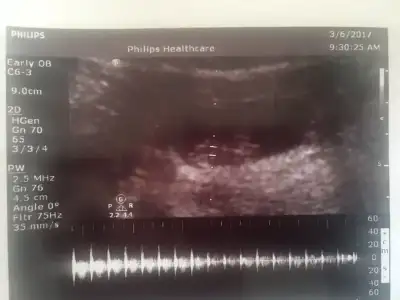

Benimkinide yorumlayin lutfen bir kizim var erkek istiyorum bu usg bugun cekildi karindan 8+4 Havalianne__ Havalianne__

20170228_201651-1-1.webp